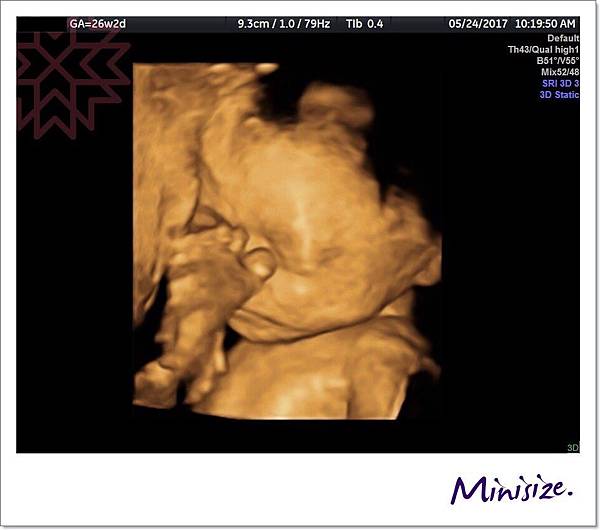

看看我的Timo寶寶近況如何

頑皮的小寶貝還用腳ㄚㄚ跟我們敬禮

小腳ㄚ真的可愛屎了 ![]()

26W2D Timo寶寶健康長大中

體重增加為945克

頭圍長大為6.59公分

大腿骨也增長為5.05公分,踹麻麻肚皮力道也越來越大

醫生說數據皆符合標準範圍內!